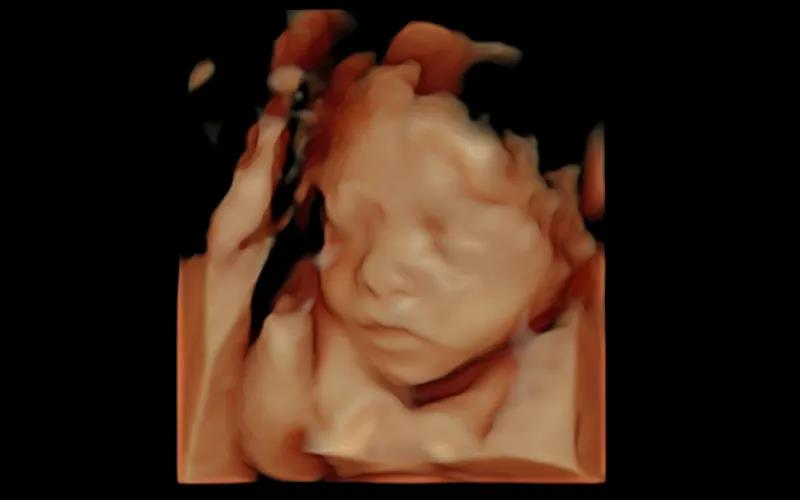

通過四維彩超

準(zhǔn)媽媽能直觀的看到胎寶寶的模樣和動(dòng)作

深呼吸,放輕松,滑滑的液體涂在肚皮上,探頭滾動(dòng)起來,屏幕上出現(xiàn)了小家伙的小腿,緊接著就是小臉,熟睡的側(cè)臉看得很清楚,這不就是我小時(shí)候的模樣嗎?像媽媽哦,開心

產(chǎn)科醫(yī)生給解說完報(bào)告后,說寶寶很好,我更開心了。感謝瑞博醫(yī)院高清四維彩超哦,聽說是美國進(jìn)口的,難怪拍出來的這么清晰!寶貝,你的健康就是我最大的幸福,這是你的第一張照片哦~

美國GE-E10四維彩超儀是瑞博醫(yī)院彩超室的“最新成員”,為給更多孕媽帶來煊光超聲體驗(yàn)而引進(jìn)!美國GE-E10四維彩超是專業(yè)婦產(chǎn)彩色超聲診斷儀(美國原裝進(jìn)口),基于創(chuàng)新的“煊光”成像系統(tǒng)架構(gòu)平臺(tái),搭載煊影成像技術(shù)和煊流成像技術(shù),配合創(chuàng)新的電子曲面矩陣四維探頭,能夠提供更多、更科學(xué)的圖像數(shù)據(jù),實(shí)現(xiàn)胎兒影像的360°動(dòng)態(tài)演示,顛覆傳統(tǒng)視覺理念,讓你看得更清晰、更直觀!